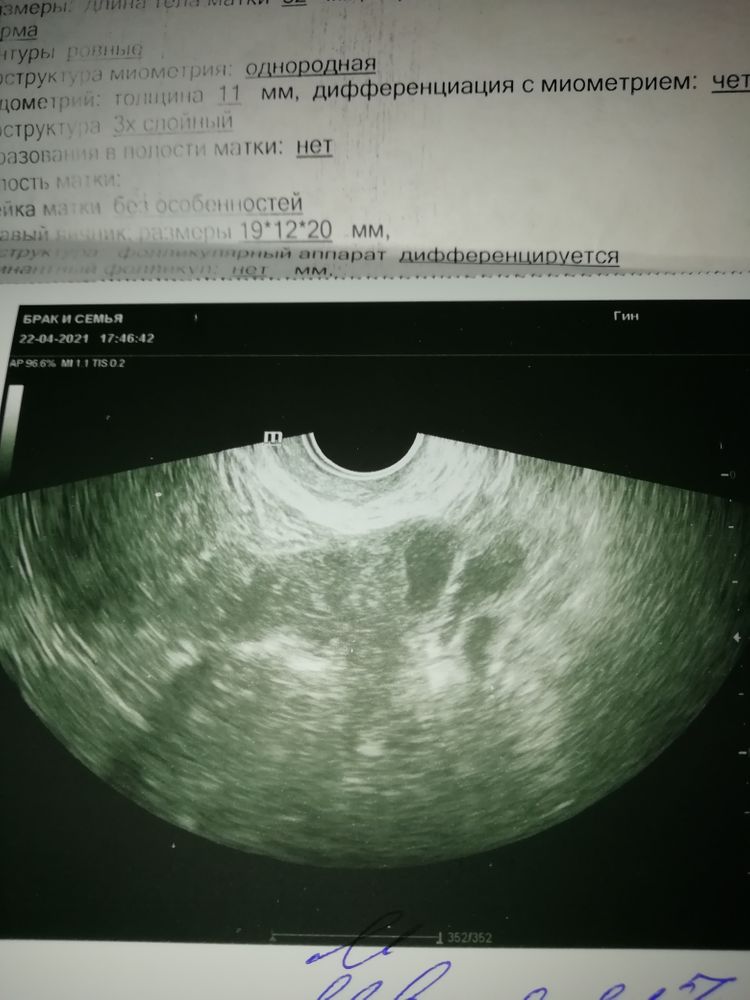

ДОПОЛНЕНИЕ. Сходила к другому узисту, которая сказала, что не видит никаких кист и что Овуляция на подходе. Эндометрия отличный. Вчера очень сильно болело с лева. Однако заключение её меня смутило. Посмотрите девочки, что скажете🤔сегодня 13дц. Так киста или дф🙄

Посмотри пожалуйста узи от 19апреля.